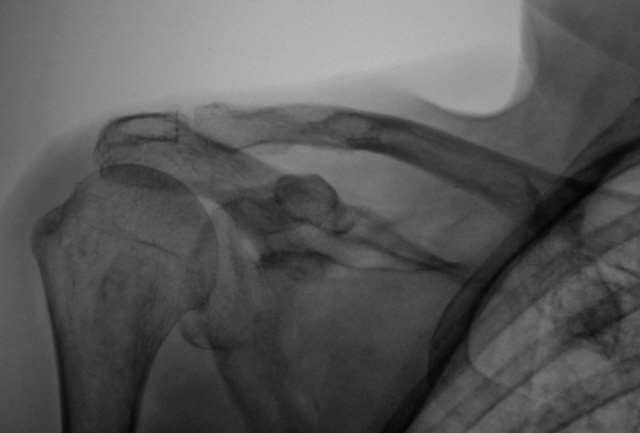

Коллеги посмотрите ключицу. Ваше мнение?

Пациентка направлена хирургом для рентгенографии плечевого сустава с диагнозом деформирующий артроз. Предъявляет жалобы на боли в области плечевого сустава.

Мне и надостная часть лопатки не нравится, и ость ее как-то вогнута книзу. Вообще, если посмотреть на первый (обзорный) снимок в целом, создается впечатление об овальном объемном образовании, исходящем из мягких тканей надостной области и давящей на ключицу снизу, а на лопатку и ее ость сверху. Как вариант, какая-нибудь рабдомиосаркома.

Спасибо Андрей Юрьевич. Я понял, что наиболее правильнее считать, что надостной ямы фактически нет, она полностью разрушена, как и разрушен верхний край лопатки,  осталась одна лопаточная ость, а именно её "зависшие остатки" и инфильтративный рост распространился на ключицу.